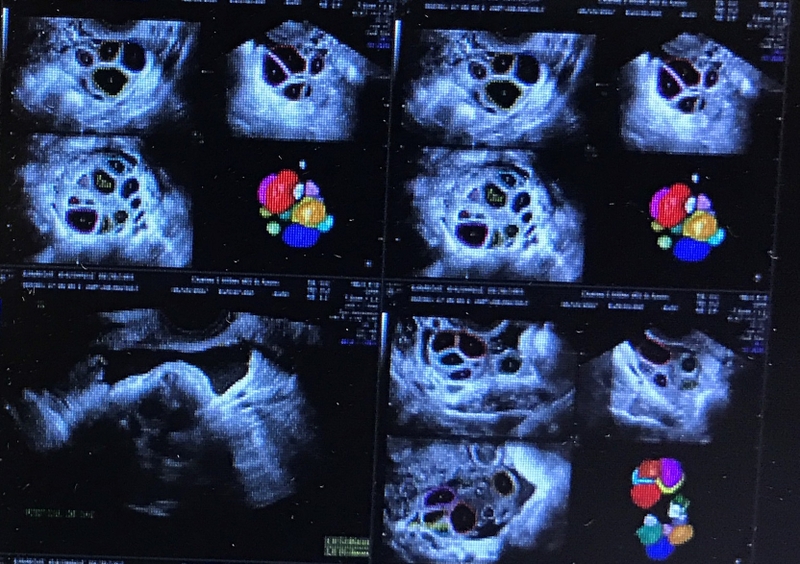

Để lấy được trứng trưởng thành để thụ tinh ống nghiệm, các bác sĩ cần chọc hút trứng. Đây được xem là một thủ thuật hỗ trợ sinh sản quan trọng, giúp lấy trứng trưởng thành đủ điều kiện thụ tinh ra khỏi buồng trứng dưới sự hướng dẫn của siêu âm. Thủ thuật chọc hút trứng được thực hiện chỉ trong khoảng 15 đến 20 phút là hoàn thành. Trứng được hút ra sẽ được đưa ngay vào phòng Lab để sẵn sàng thực hiện các bước tiếp theo của thụ tinh ống nghiệm.